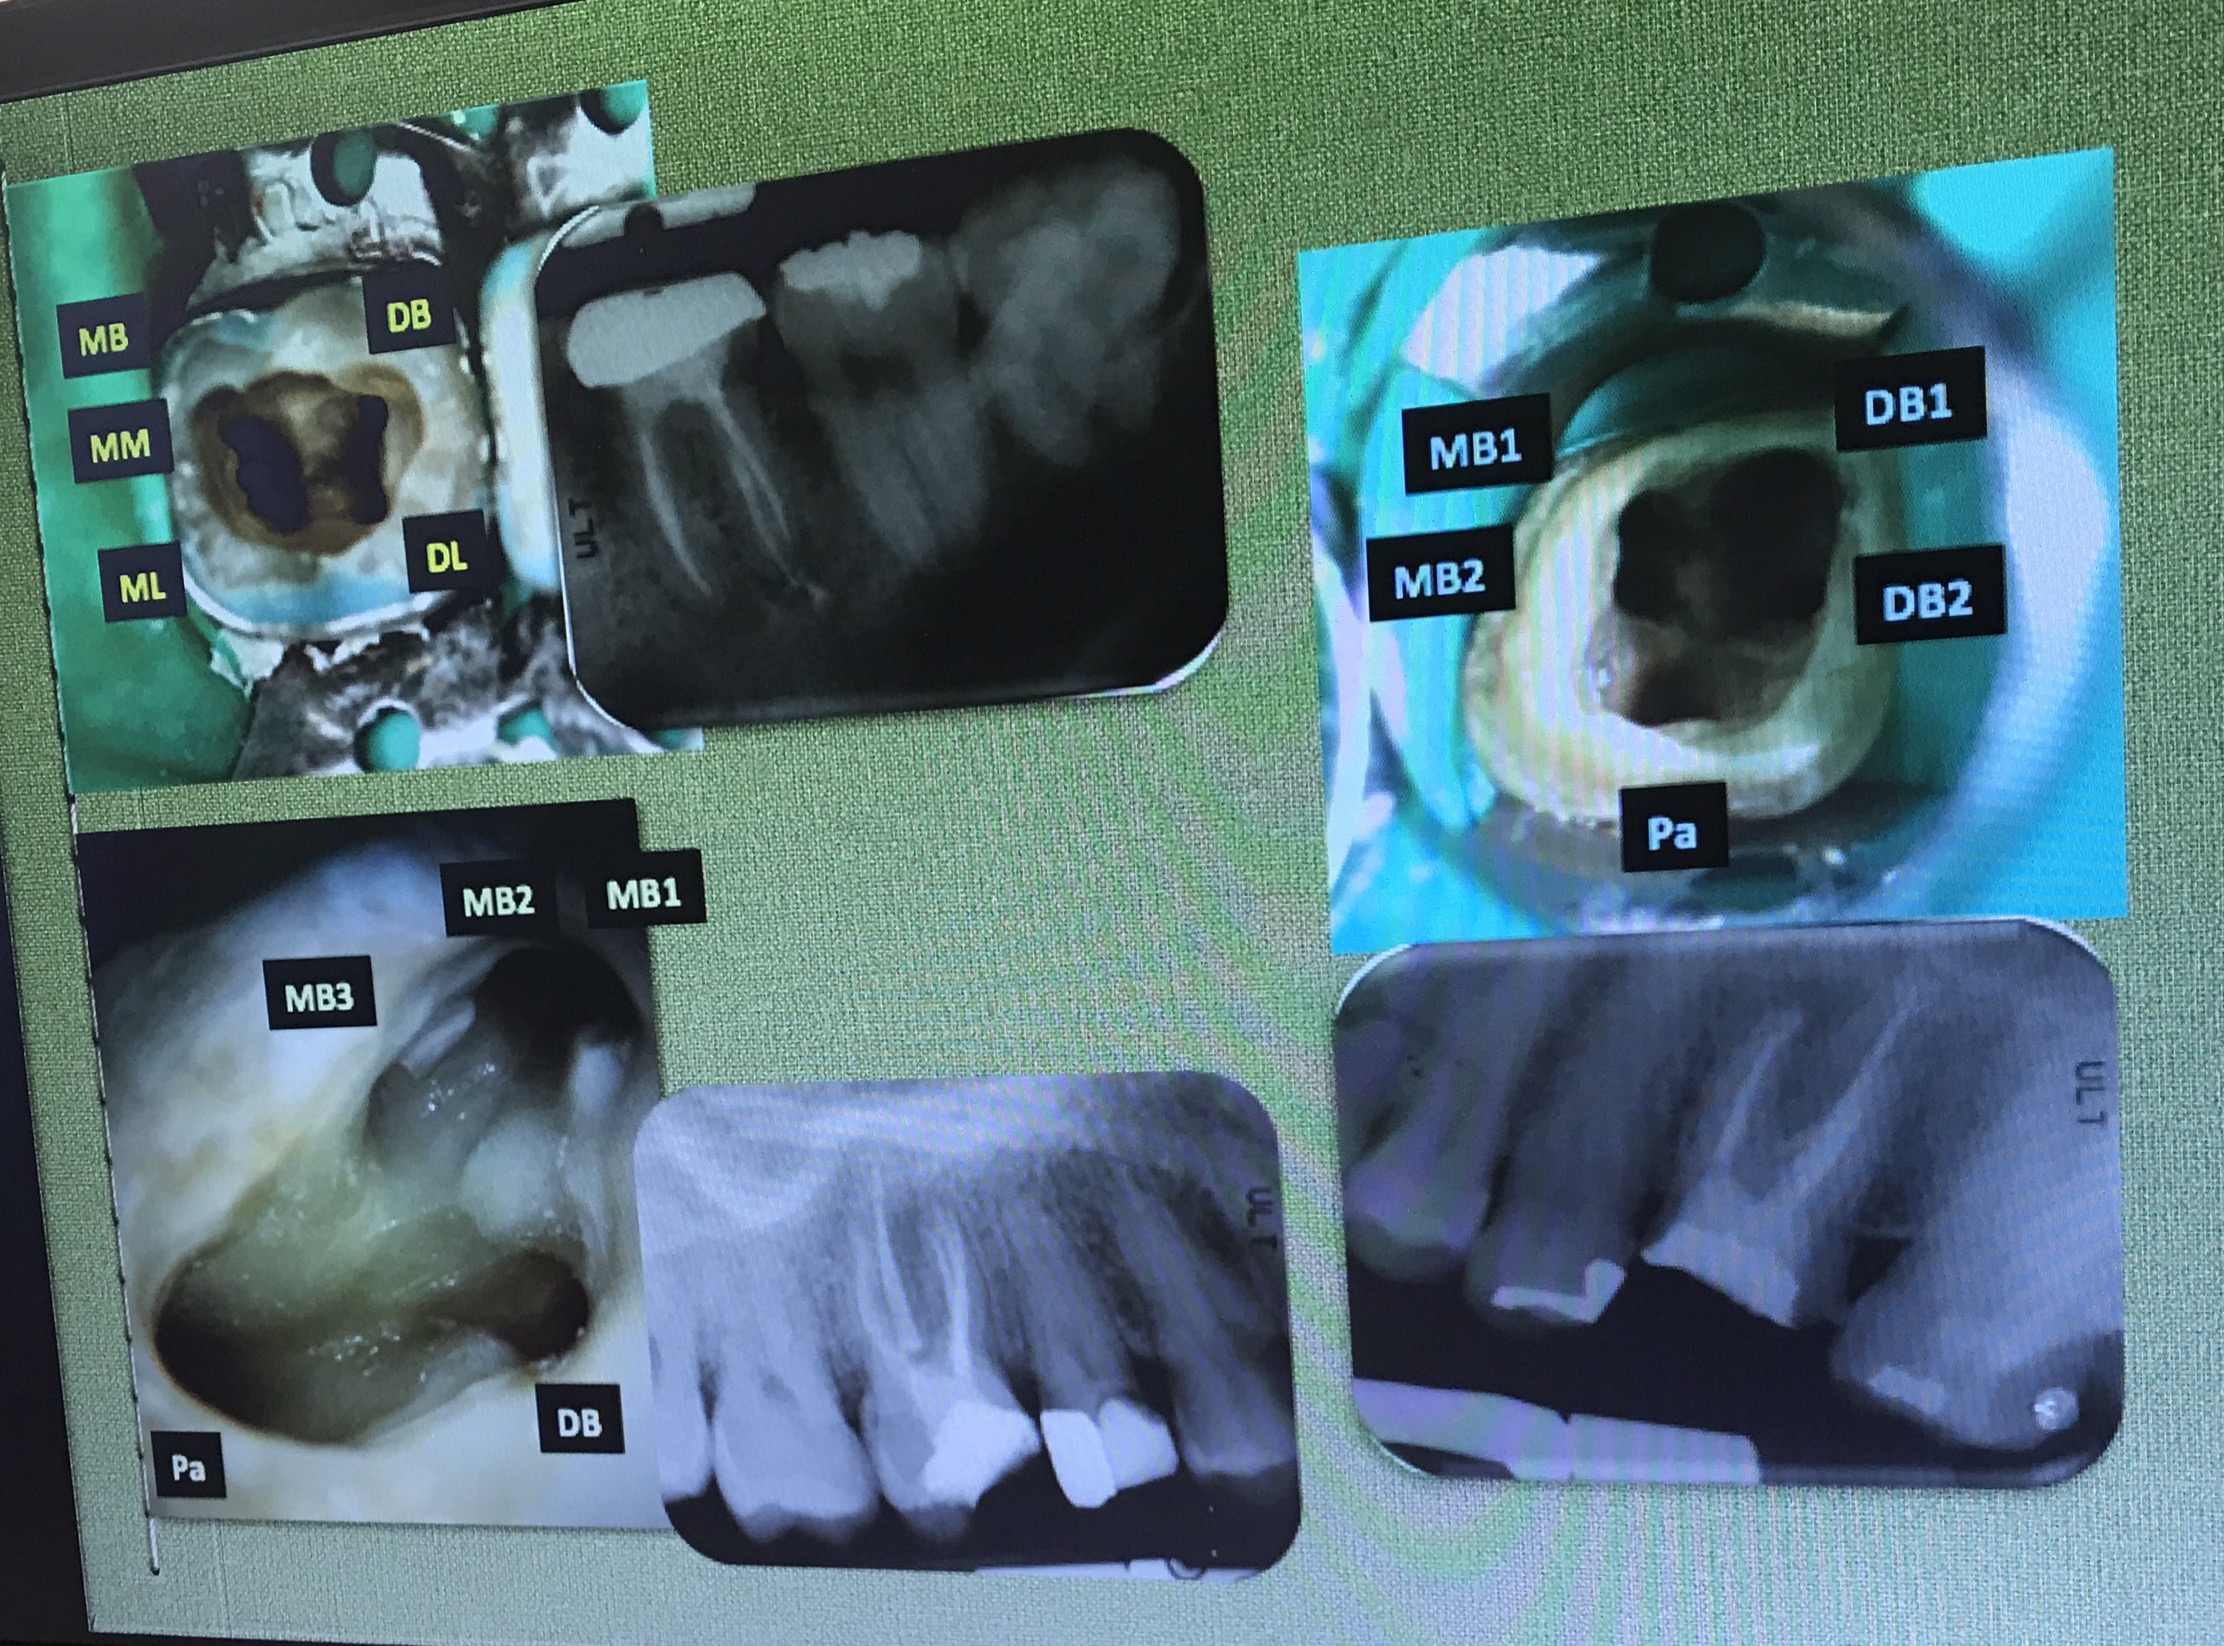

ฟัน #36, 46 คือฟันที่ท่านอาจารย์เตรียมไว้ให้สำหรับการฝึกการรื้อเครื่องมือและการซ่อมรอย perforate ในช่วงบ่าย

งานที่ใช้เยอะมาก การ Locate canal หา MB2

อย่างที่บอก ท่านอาจารย์แนะนำว่า ควรมี Mind set ไว้ในใจว่า ฟัน molar บน จะมี MB2 อยู่ในตำแหน่งที่ค่อนมาทาง Palatal ต่อ MB1 เล็กน้อย

ฟันที่มี MB2 อยู่ที่ 95.2% (ซึ่งจะเห็นว่าเยอะมาก)

ถ้าเราใช้ตาเปล่าหา MB2 จะมีโอกาสเจอที่ 17.2%

แต่ถ้าใช้ MC จะมีโอกาสหาเจอเพิ่มขึ้นเป็น 71.1%

ตำแหน่ง MB2 จะห่างจาก MB1 ไม่มาก

ทิศทางการกรอ จะไม่ remove ส่วน floor ครับ แต่กำจัดเฉพาะส่วนที่ Calcified

ลองสังเกตเส้นที่ลาก ตำแหน่งของ MB2 จะอยู่ mesial ต่อเส้นนี้ที่ระยะประมาณ 1-2.5 มม.

แนวเส้นประสีแดง คือ บริเวณที่จะพบ MB2